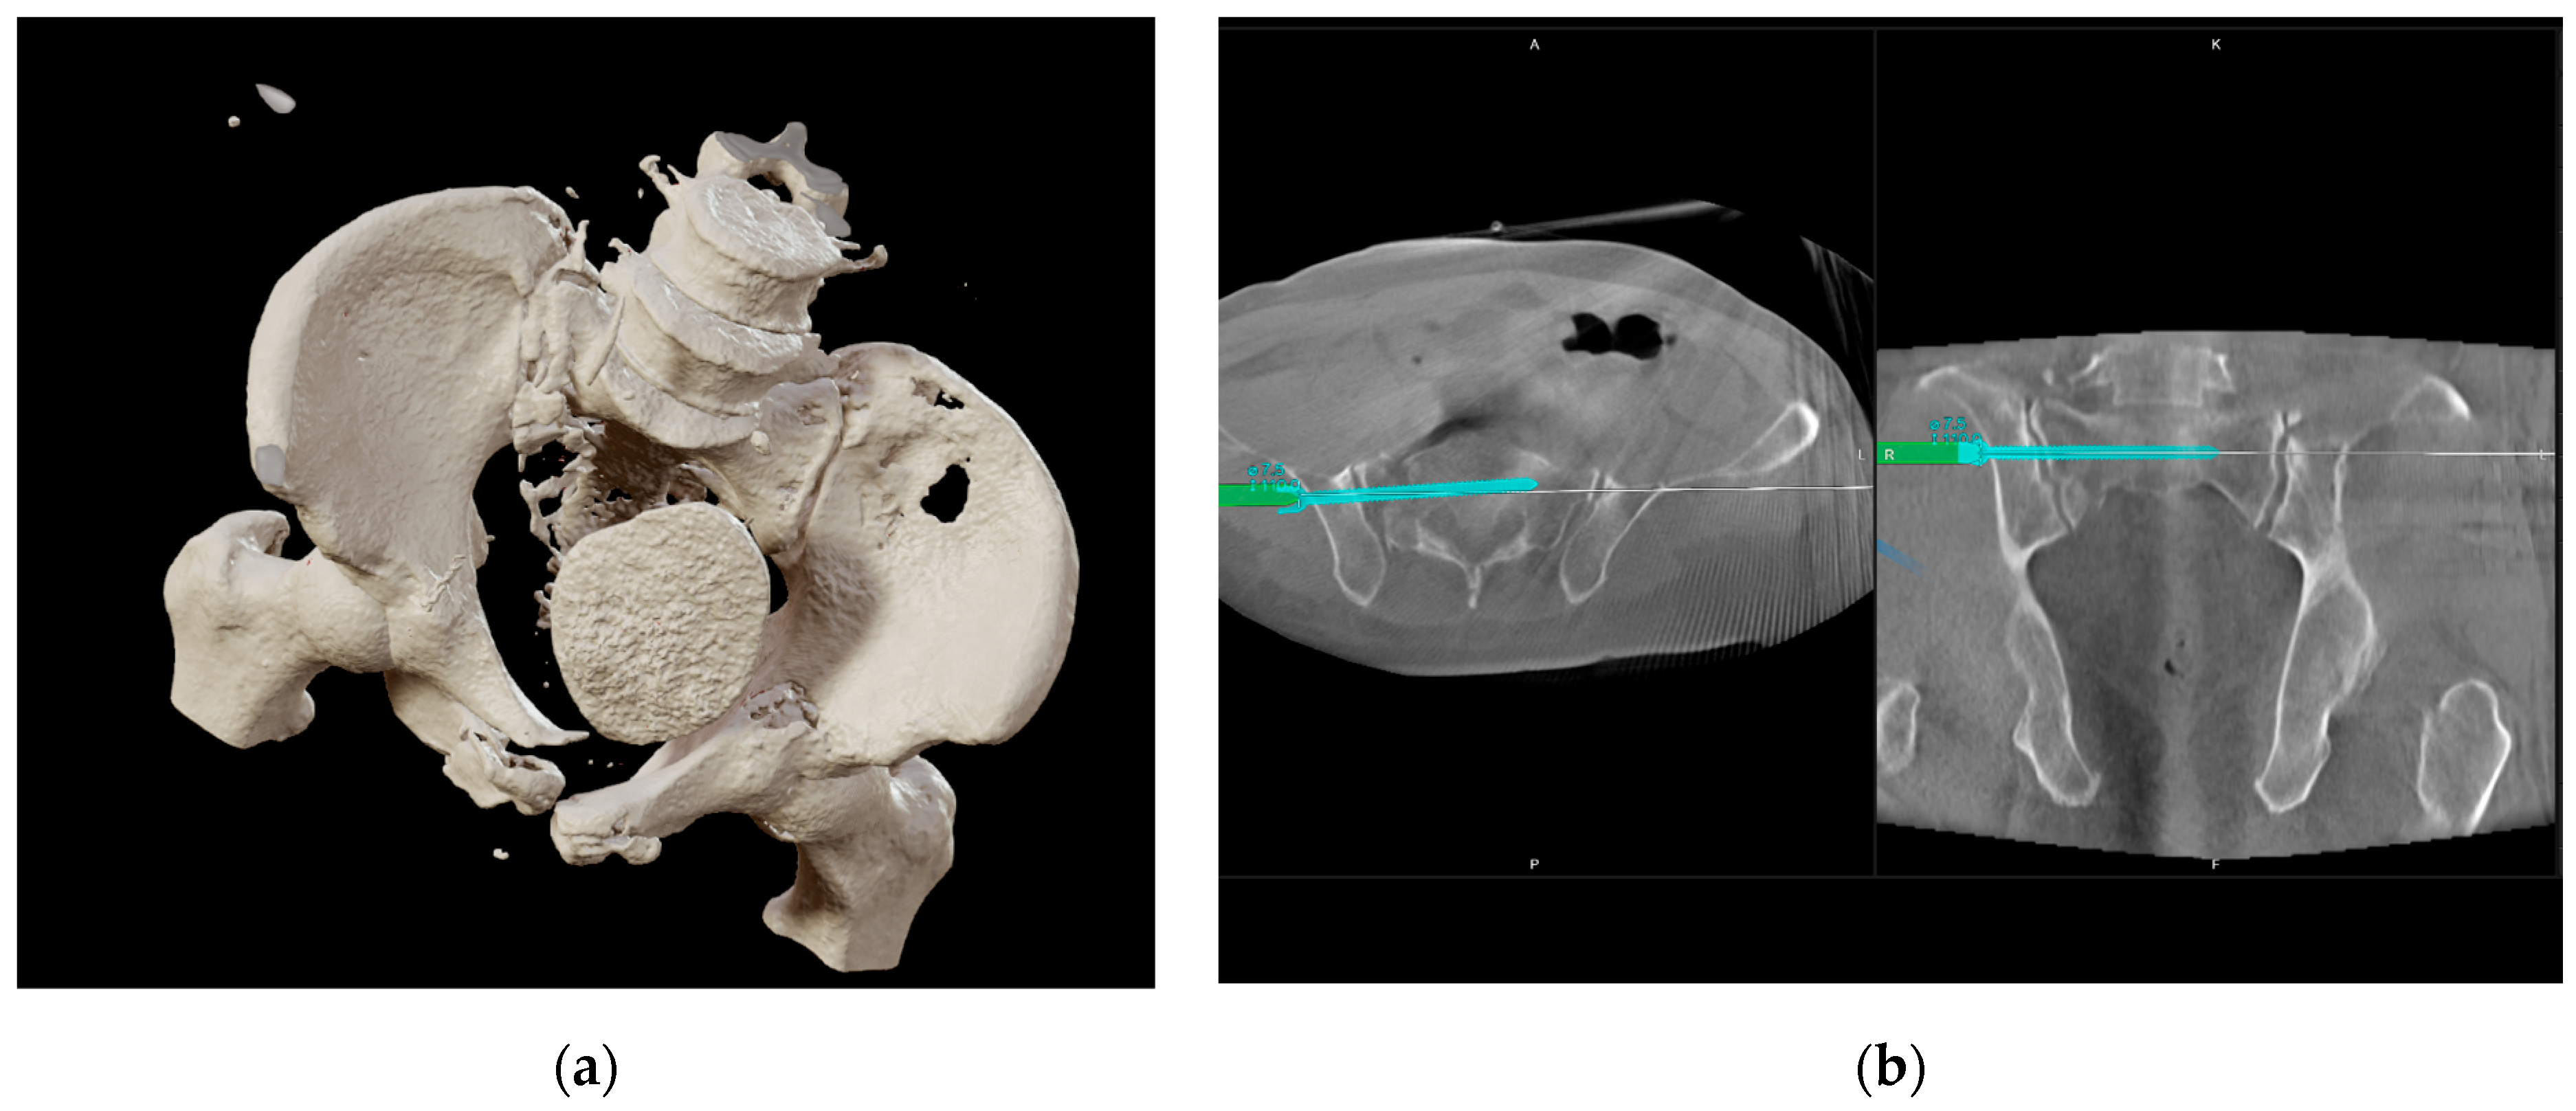

2.2. Injury Details and Initial Treatment

2.3. Indication

3.2. Intervention

3.5. Fracture Repositioning and Osteosynthesis

3.6. Outcomes